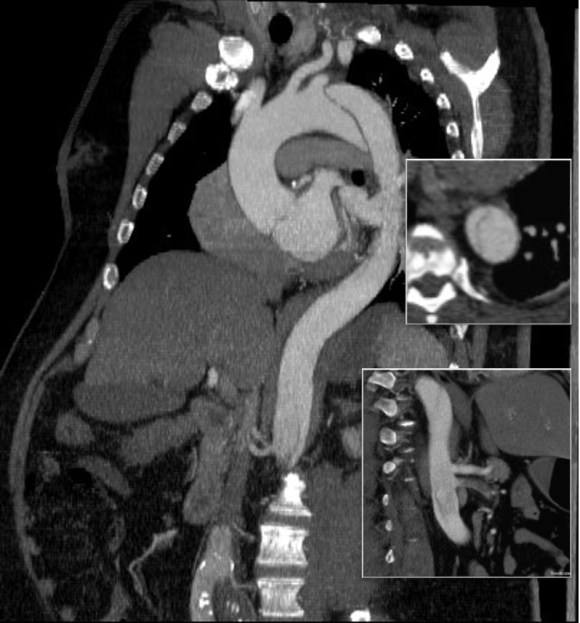

The operation went well. The patient’s angina resolved and a followup CT showed the patent bypass feeding the LIMA and LAD.

At its heart, it would be this vascular surgeon’s attempt at an off-pump single vessel CABG (above). Preparations were made with cardiac anesthesia and cardiac surgery to place an IABP (intra-aortic balloon pump) if he became unstable. For my part, the operation was straightforward, but I was going to have to go about it efficiently. I also figured that with a clamp beyond the LIMA takeoff, no significant change would occur to the coronary flow from the LIMA graft. So I hoped as I worked very deliberately. We kept him on the hypertensive side during the case.